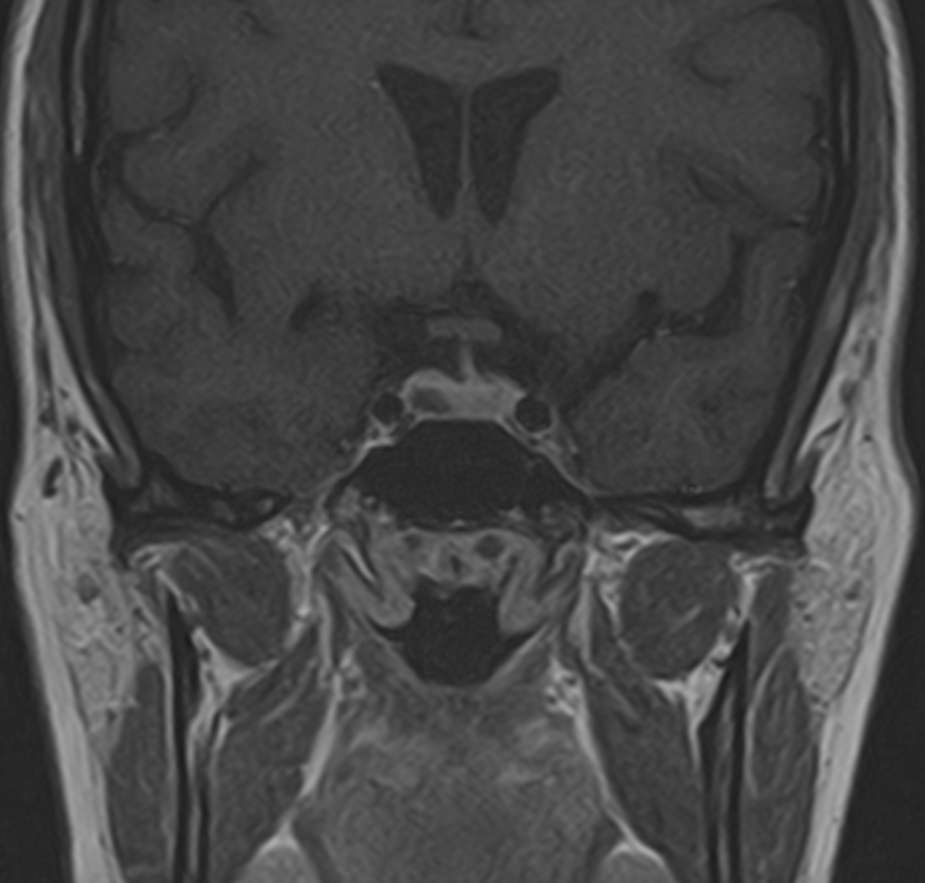

МРТ головного мозга позволяет оценить состояние всех структур головного мозга, однако для выявления патологии гипофиза назначается дополнительно МРТ гипофиза с прицельным осмотром области турецкого седла. Это два разных обследования, каждое из которых имеет свой протокол сканирования. Причем в подавляющем большинстве случаев МРТ гипофиза проводится с контрастным усилением, так как без этого данное исследование малоинформативно.

Опухоли гипофиза являются достаточно часто встречающейся патологией, особенно у людей молодого и среднего возраста. При этом выявляются как злокачественные, так и доброкачественные новообразования. В большинстве случаев обнаруживаются аденомы гипофиза (доброкачественные образования). При проведении стандартной МРТ головного мозга можно выявить достаточно большие опухоли гипофиза (от 1 см), а для выявления опухолевых образований меньших размеров (микроаденом) требуется МРТ гипофиза с контрастным усилением.

Метод позволяет создавать детализированные изображения всех структур головного мозга, в том числе области турецкого седла, и по праву считается лучшим способом диагностики любых объемных образований гипофиза. С помощью МРТ головного мозга и гипофиза можно выявить макроаденомы и большинство микроаденом (размером до 3мм).